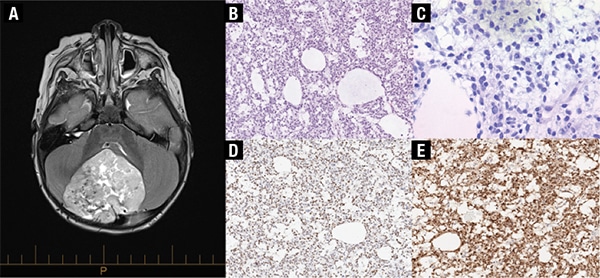

Case report. A previously healthy and ambulating 18-month-old female presented to our institution with a history of progressive ataxia over the prior few weeks. A large well-demarcated mass (5.6 × 6.0 × 6.4 cm) in the midline cerebellum was detected on MRI with no metastases identified (Fig. 1A). The patient underwent a posterior fossa craniotomy with gross total resection. Histologic examination showed poorly differentiated tumor cells with high nuclear-to-cytoplasmic ratios and round to oval and irregular hyperchromatic and vacuolated nuclei arranged in a reticular architecture with scattered microcystic spaces and a prominent myxoid background (Fig. 1B–C). Patchy areas of hemorrhage and necrosis along with scattered microcalcifications were present. There were frequent mitotic figures (22 per 10 high-power fields), and the Ki-67 proliferative index was high at approximately 60 percent. The tumor cells showed neuroepithelial differentiation with immunoreactivity for synaptophysin and NeuN (Fig. 1D–E). The tumor cells were also immunoreactive for GAB1 (cytoplasmic) and YAP1 (nuclear and cytoplasmic), with only cytoplasmic beta-catenin immunoreactivity, providing evidence of SHH (Sonic Hedgehog) signaling pathway activation via immunohistochemistry. GFAP highlighted scattered entrapped glial cells. No malignant cells were seen on cytological examination of the cerebrospinal fluid.

As a diagnosis of HGNET was suspected, Sanger sequencing of exon 15 of the BCOR gene was performed on DNA isolated from fresh frozen tumor tissue. An in-frame internal tandem duplication in exon 15 of the BCOR gene, c.4997_5110dup (p.Leu1703_Gly1704ins38), was detected (Fig. 2A–C). Additional testing included microarray analysis, which showed loss of the entire chromosome 3 long arm, and chromosome analysis (Fig. 2D), which showed an unbalanced translocation involving chromosome 3 and 21 with loss of 3q (46,XX,der(3;21)(q10;q10)[6]; 46,XX[14]). This karyotypic abnormality was not a known recurrent aberration associated with any particular tumor type. Additional reference laboratory testing showed the tumor cells had strong diffuse nuclear immunoreactivity for BCOR. BCOR rearrangement was not detected by fluorescence in situ hybridization testing. However, approximately three percent of the nuclei showed three BCOR signals, consistent with a duplication.